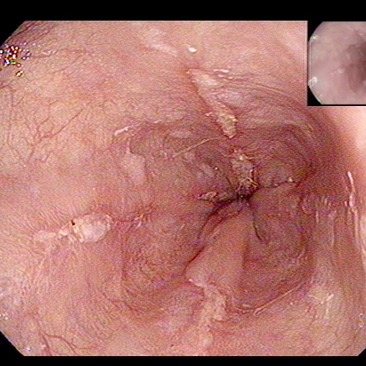

궤양 출혈로 수회 입원하였으나 제균치료를 하지 않았다? 위내시경 확인하여 투약하고 제균여부를 확인함 - 동대문구 답십리, 전농동, 우리안애 우리안愛 내과

"병원 혈당, 보통 식후 200 정도였다"?? A1c에 대해 모름, "검사하면 괜찮다고.." ; 초진때의 언급인데... 공복이 300 이상인데 괜찮다? 괜찮지 않은것을 괜찮다고 얘기하는 무관심이 아니었을지? https://blog.naver.com/ejercicio/223811612764 "이전 병원에서 당뇨 심각하게 얘기하지 않던데.." "이전 병원에서 당뇨 심각하게 얘기하지 않던데.. : 네이버블로그 ... 궤양 치료? 로 입퇴원을 반복하여 체중이 빠진.. : 네이버블로그 상기 환자 위궤양 출혈이 재발하지 않아서 인지... 체중도 증가하면서 빈도는 많지 않았으니 공복 혈당과 식후 혈당이 올라가는것 처럼 보인다. 26.2월 검사시 당화혈색소는 7.4로서 증가하여 3제 경구약제중에 하나를 변경함 ; 이후 식후 혈당은 160~180 정도로 확인되는데... 가정혈당을 측정하지 않아 확정적일지는 좀더 관찰이 필요하다. 기존 병원에서 의무기록 사본 발부를